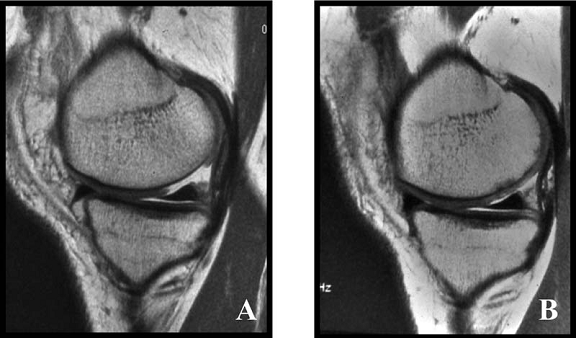

Fig.34. A-scanare inaintea microfracturarii, B-scanare la patru luni dupaa microfracturare.

Evaluarea imaginilor RMN a fost realizata de catre radiologist cu experienta, care cunostea situatia pacientilor si operatia efectuata. Imaginile au fost astfel analizate incat sa se observe zonele cu cartilaj de reparare comparativ cu cel nativ. Repararea morfologica a fost descrisa ca depresiva, neteda, sau mareata comparativ cu cartilajul nativ inconjurator. Volumul de umplere al defectului cu cartilaj reparator a fost masurat folosind imagini sagitale si coronale si a fost gradat ca bun (intre 67% si 100%), moderat (34% la 66%), sau slab (0% la 33%) pe baza procentajului defectului umplut. Interfata cu suprafata cartilajului nativ adiacent a fost evaluata si gradata ca fiind mica ( gaura ≤ 2mm) sau mare (gaura ˃ 2mm). Edemul maduvei osului subcondral a fost gradat ca fiind usor (˂ 1 cm²), moderat (intre 1 si 3 cm²) sau sever (˃ 3 cm²), iar prezenta sau absenta cresterii osoase a fost atent inregistrata.